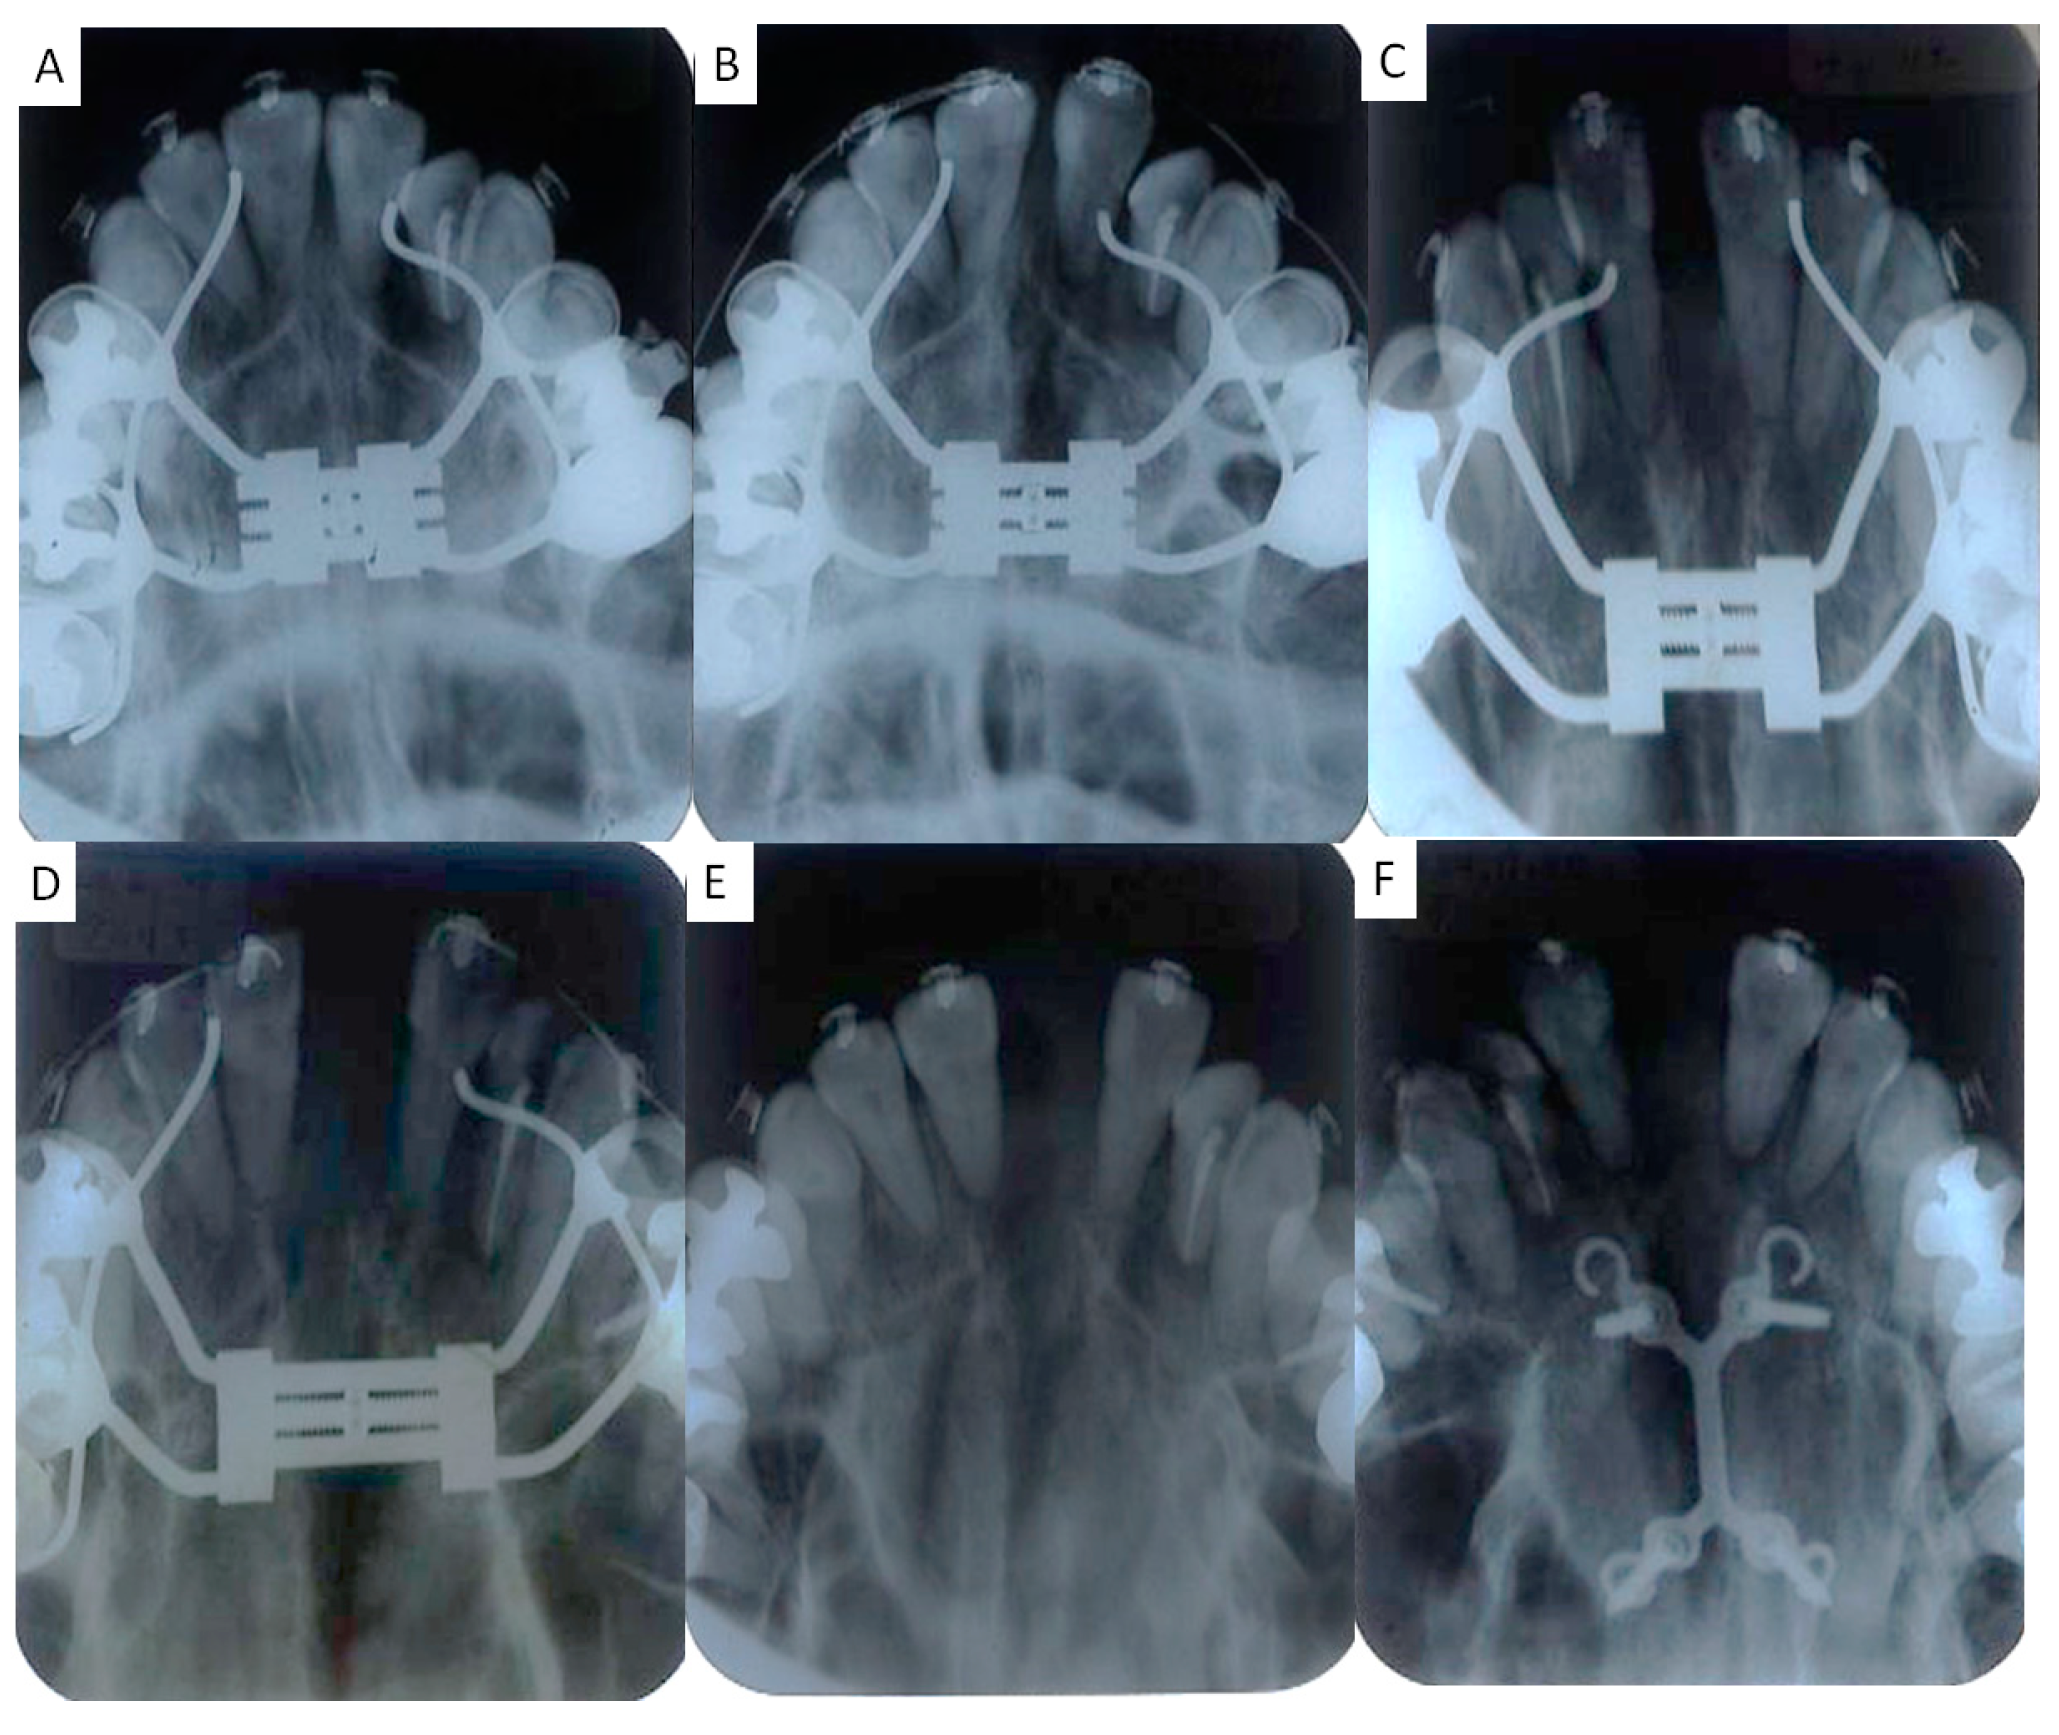

2.3. Treatment Progress